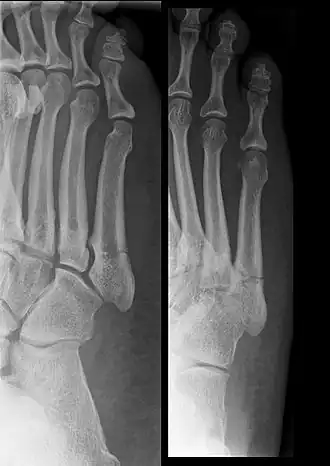

Een jonesfractuur is een botbreuk van het middenvoetsbeen van de kleine teen (het os metatarsale V). Bij een jonesfractuur is dit bot gebroken aan proximale zijde. De breuk bevindt zich dus halverwege aan de buitenkant van de voet. De patiënt heeft daar pijn en zwelling en zal moeite hebben met lopen. Maar de hinder kan soms meevallen, zodat de patiënt denkt een kneuzing te hebben. Om de diagnose te stellen zal een röntgenfoto van de voorvoet gemaakt moeten worden.

De 'echte' jonesfractuur moet onderscheiden worden van de twee andere vaak voorkomende fracturen van het os metatarsii V. Enerzijds een avulsiefractuur veroorzaakt door de musculus peronaeus brevis, nog dichter bij het proximale uiteinde van het bot gelegen. Deze fractuur geneest veel gemakkelijker, ook zonder immobilisatie. Anderzijds een diafysale stressfractuur. Deze fractuur is in tegenstelling tot de jonesfractuur eerder chronisch van aard en vereist vaak een fixatie of een autogene bottransplantatie.[1] Breuken halverwege of distaal van het vijfde middenvoetsbeentje komen veel minder vaak voor.